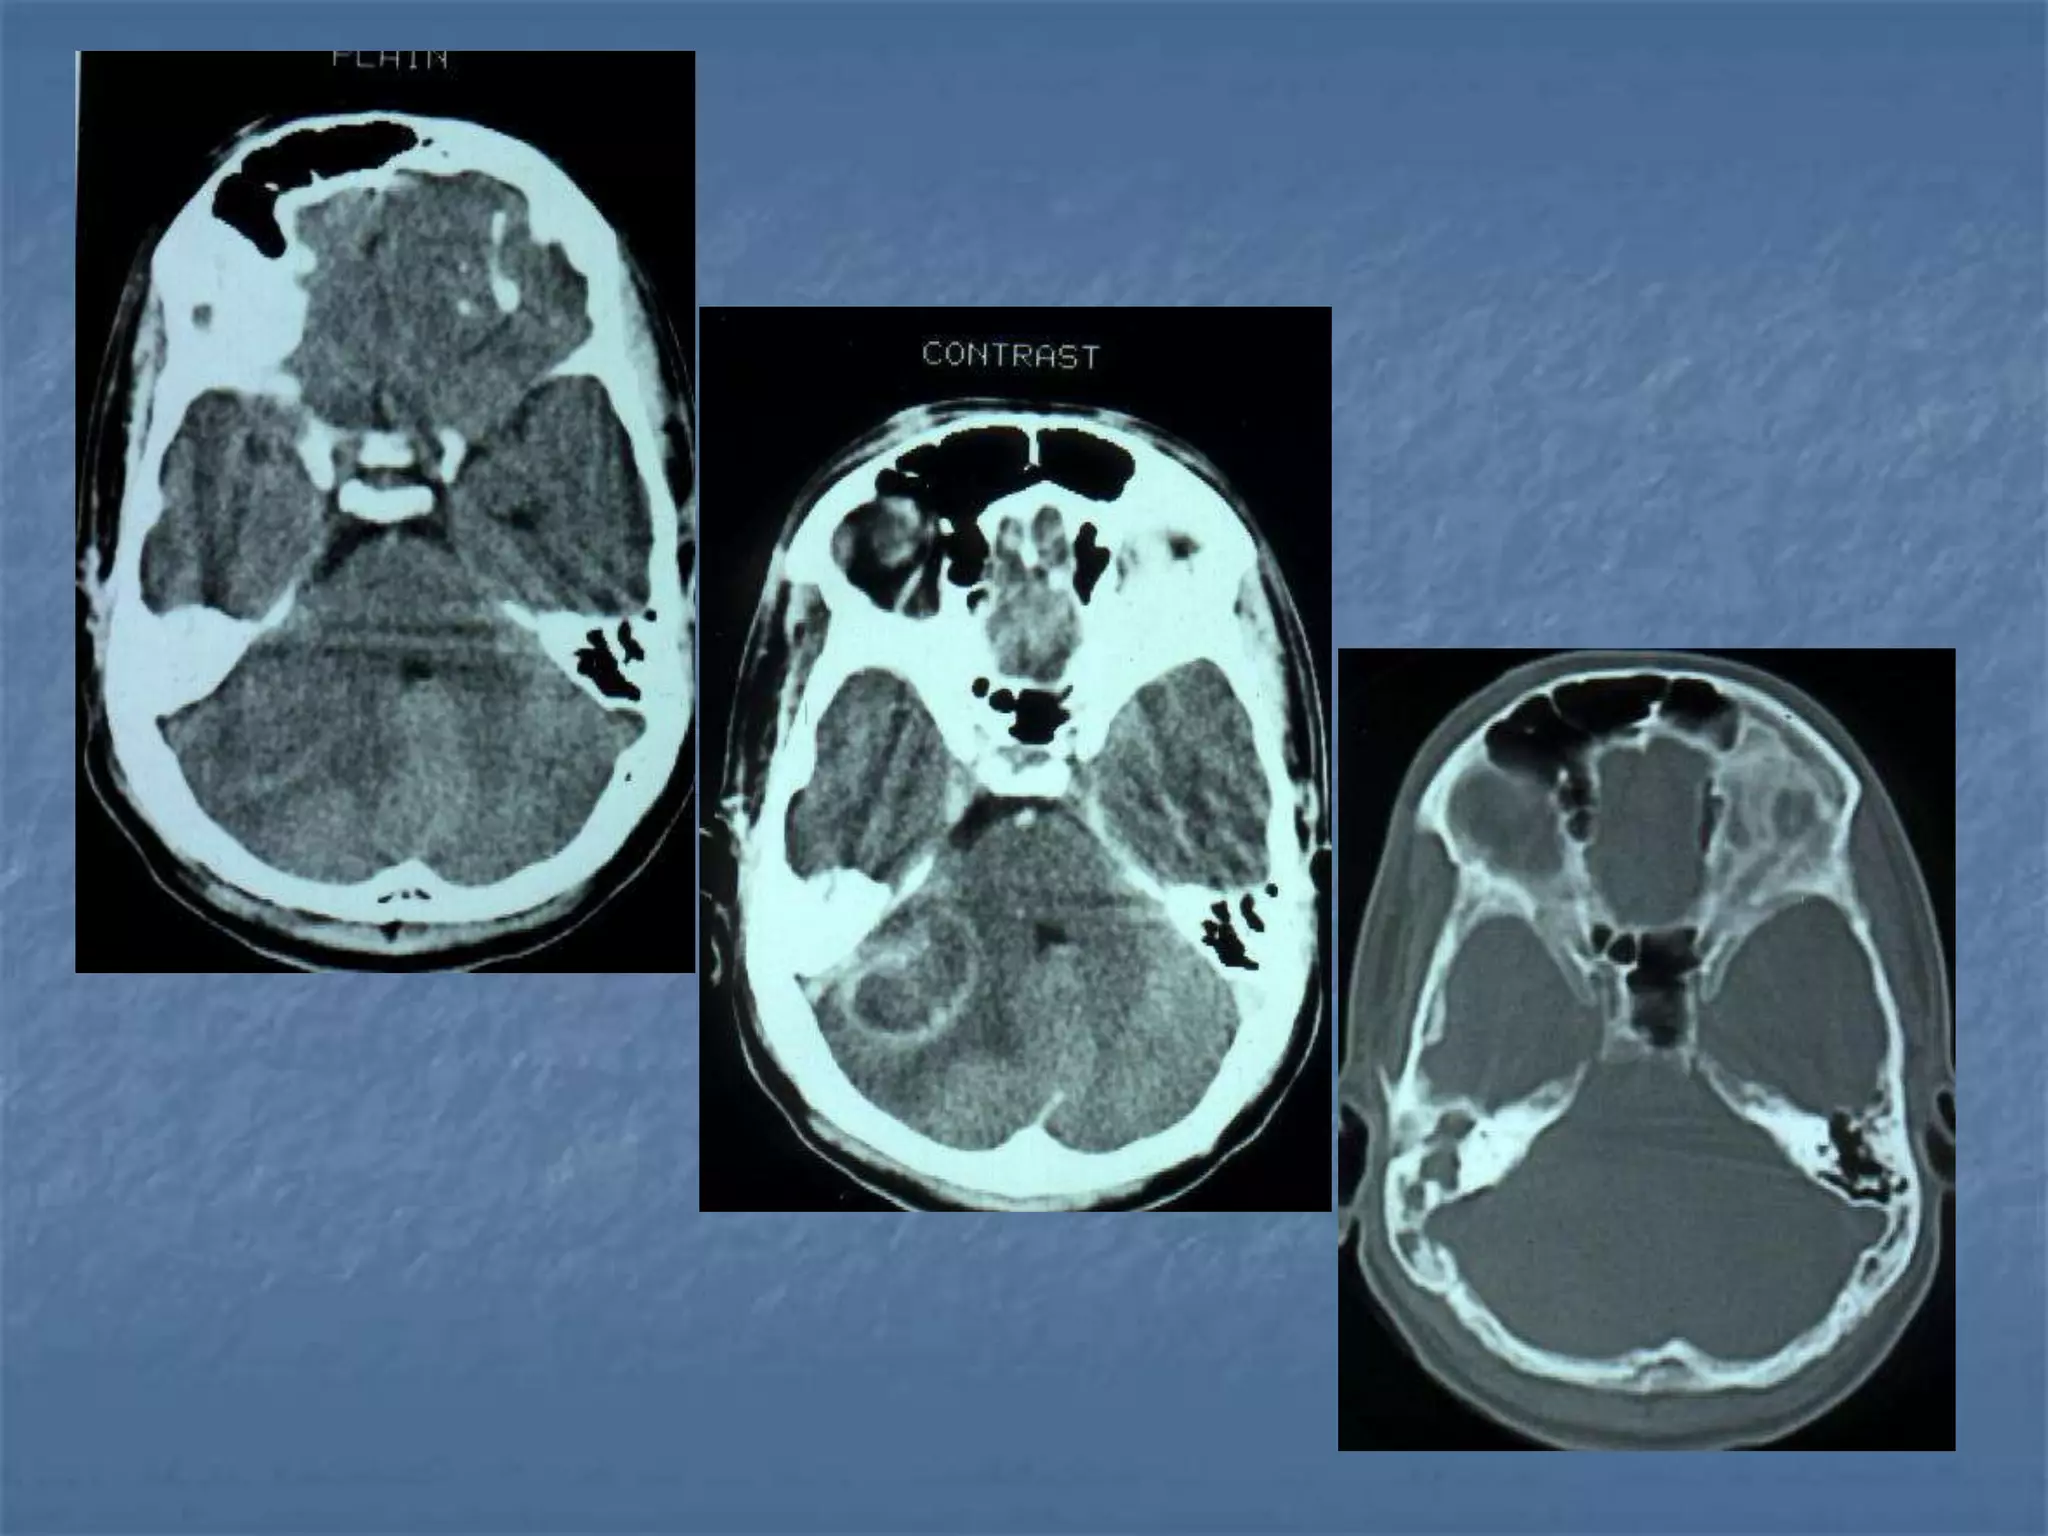

ARTERIOVENOUS MALFORMATION